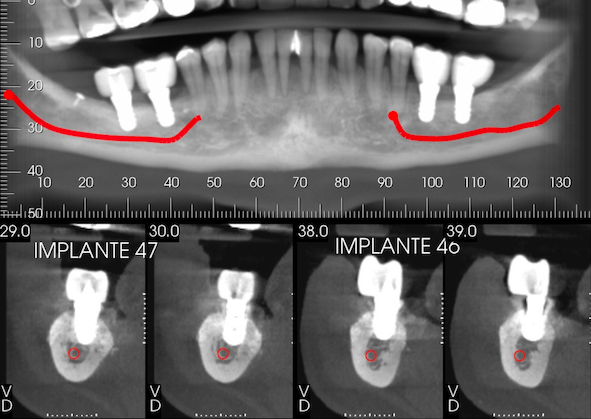

After one month from the surgical procedure, a T-plate was placed (Neodent®, Curitiba, PR, Brazil) in the buccal region and also a mini-implant (Neodent®, Curitiba, PR, Brazil) in the palatal region between teeth #17 and #18 (Fig. 6a). Moreover, two brackets (Morelli, Sorocaba, SP, Brazil) were also bonded to these teeth for activation of the plate and mini-implant in order to intrude them, thus creating space for placement of the prostheses (Fig. 6b). After six months, another CBCT was performed to assess the vertical and horizontal reconstruction. There was vertical bone augmentation in the region of teeth #46 and #47, respectively, by 2.68 mm and 3.21 mm (Fig. 7), which allowed the placement of 6-mm implants. The same medication and anaesthetic protocol used in previous surgery were used for this surgical step. A mucoperiosteal incision in the alveolar crest was performed (Fig. 8a), followed by a detachment of the flap and placement of two implants of 4.1 x 6.0 mm (Standard Plus SLActive, Roxolid®, Straumann, Basel, Switzerland) according to the manufacturer’s instructions (Fig. 8b) and (Fig. 8 and c). Post-operative medication and guidance were the same used after placement of implants on the contralateral side.

In this clinical case, the GBR technique with pericardium membrane and ABBM mixed with autogenous particulate bone at 1:1 was used to increase the vertical bone sufficiently for placement of a short implant since the patient had a remaining bone height of 3-4 mm in the region of teeth #46 and #47 and because the bone defect was missing four bone walls. It was in the posterior region of the mandible, which is generally poorly vascularized. The resorbable membrane was chosen to avoid complications, which might occur with non-resorbable ones, such as exposure of the membrane, and because there was no need for a greater bone augmentation since the patient had a residual bone of 3-4 mm in the region. Therefore, two 6-mm implants were placed on the site. The bone increase achieved was 2.63 mm and 3.18 mm. This result is in accordance with a systematic review and meta-analysis performed by Urban et al. [8], who reported a vertical bone gain of 3.51 mm by using the GBR technique and the use of a resorbable collagen membrane.